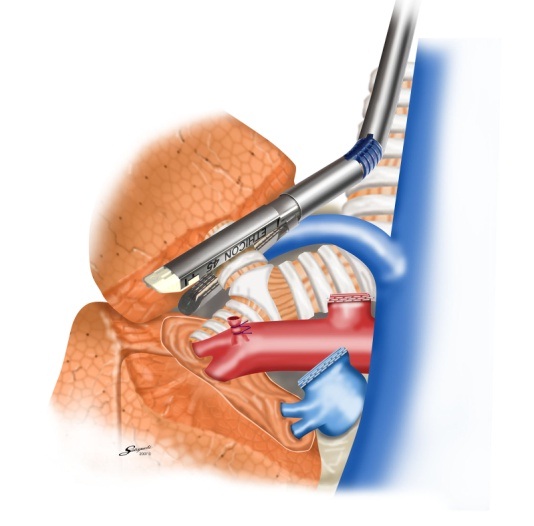

胸腔鏡手術の実際(右肺上葉切除時の自動縫合器使用例)

肺静脈切離

肺動脈切離

気管支切離

葉間切離